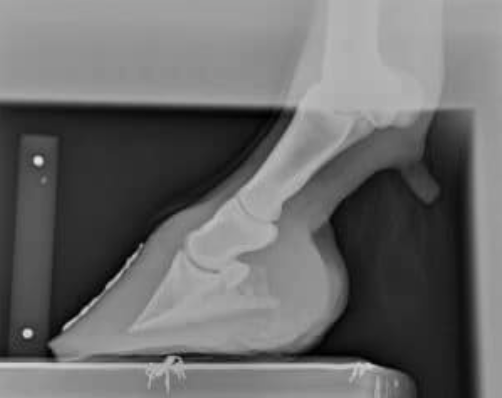

3. Consider dental issues.

To prolong the usefulness of your horse’s dentition, veterinarians and nutritionists alike recommend scheduling annual to biannual oral exams, especially in older horses. This allows you to address dental irregularities early, before they snowball into bigger issues that affect digestion and, ultimately, body condition and overall health.

Be sure to schedule annual or biannual oral exams for senior horses. Animals with declining dentition might need soaked hay pellets, hay cubes, soaked beet pulp or soaked complete senior feeds.